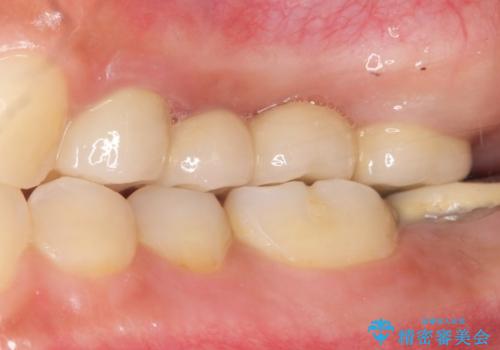

被せ物の種類:メタルボンドクラウン エコノミー フルベイク